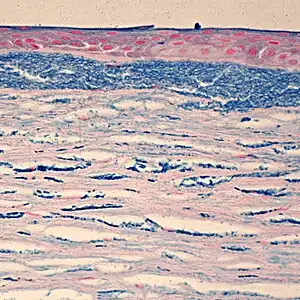

| Colloidal iron staining shows deposition of glycosaminoglycans in the cornea | |

The diagnosis of this condition is done histopathologically upon intracytoplasmic accumulations of non-sulfated keratan sulfate.[5]